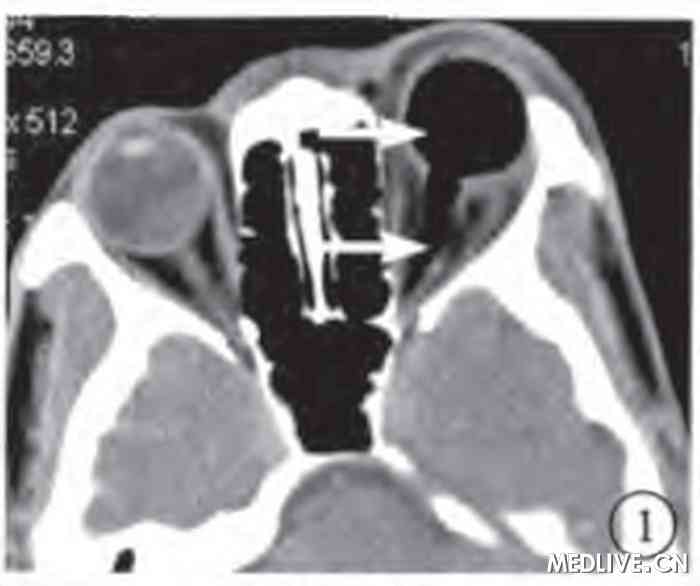

图1 玻璃体腔气体抽出手术前左眼CT横断面软组织窗像。玻璃体腔、视神经鞘内充满低密度气体 (白箭),视神经显示不淸,眼球前突。

图2 玻璃体腔气体抽出手术前左眼CT矢状面重建骨窗像。玻璃体腔、视神经鞘内、视交叉鞍上池内积气(白箭),视神经隐约显示。